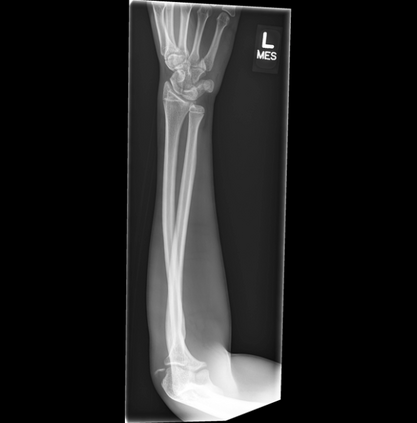

In this study, we aim to initiate the development of Radiology Foundation Model, termed as RadFM.We consider the construction of foundational models from the perspectives of data, model design, and evaluation thoroughly. Our contribution can be concluded as follows: (i), we construct a large-scale Medical Multi-modal Dataset, MedMD, consisting of 16M 2D and 3D medical scans. To the best of our knowledge, this is the first multi-modal dataset containing 3D medical scans. (ii), We propose an architecture that enables visually conditioned generative pre-training, allowing for the integration of text input interleaved with 2D or 3D medical scans to generate response for diverse radiologic tasks. The model was initially pre-trained on MedMD and subsequently domain-specific fine-tuned on RadMD, a radiologic cleaned version of MedMD, containing 3M radiologic visual-language pairs. (iii), we propose a new evaluation benchmark that comprises five tasks, aiming to comprehensively assess the capability of foundation models in handling practical clinical problems. Our experimental results confirm that RadFM significantly outperforms existing multi-modal foundation models. The codes, data, and model checkpoint will all be made publicly available to promote further research and development in the field.